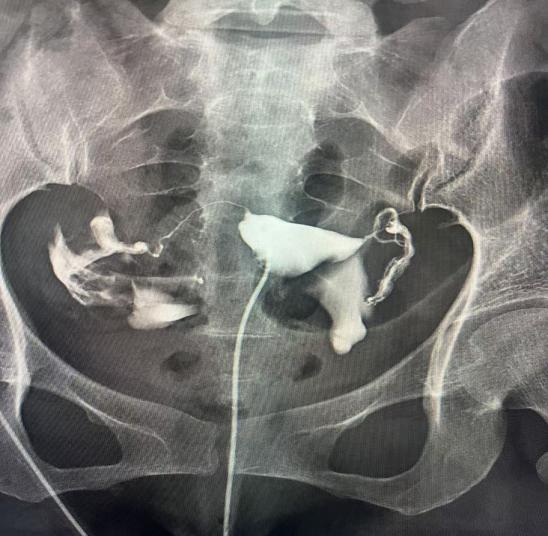

一、什么是子宮輸卵管造影?

子宮輸卵管造影是通過導(dǎo)管經(jīng)陰道、子宮頸向?qū)m腔及輸卵管內(nèi)注入造影劑,利用X線診斷儀透視并拍片,根據(jù)造影劑在子宮、輸卵管及盆腔內(nèi)的顯影情況,來了解和判斷子宮腔形態(tài),是否畸形、粘連,輸卵管是否通暢,以及輸卵管阻塞的部位。常用于不孕癥、輸卵管再通、子宮畸形等疾病的診治。如